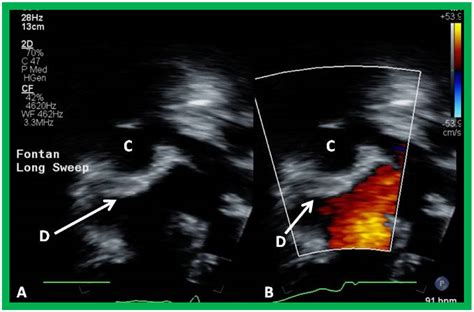

3. The Fontan Procedure: Typically performed between ages 2 and 5, this creates a final pathway for blood returning from the lower body to flow directly into the pulmonary arteries.

• double inlet lv fontan